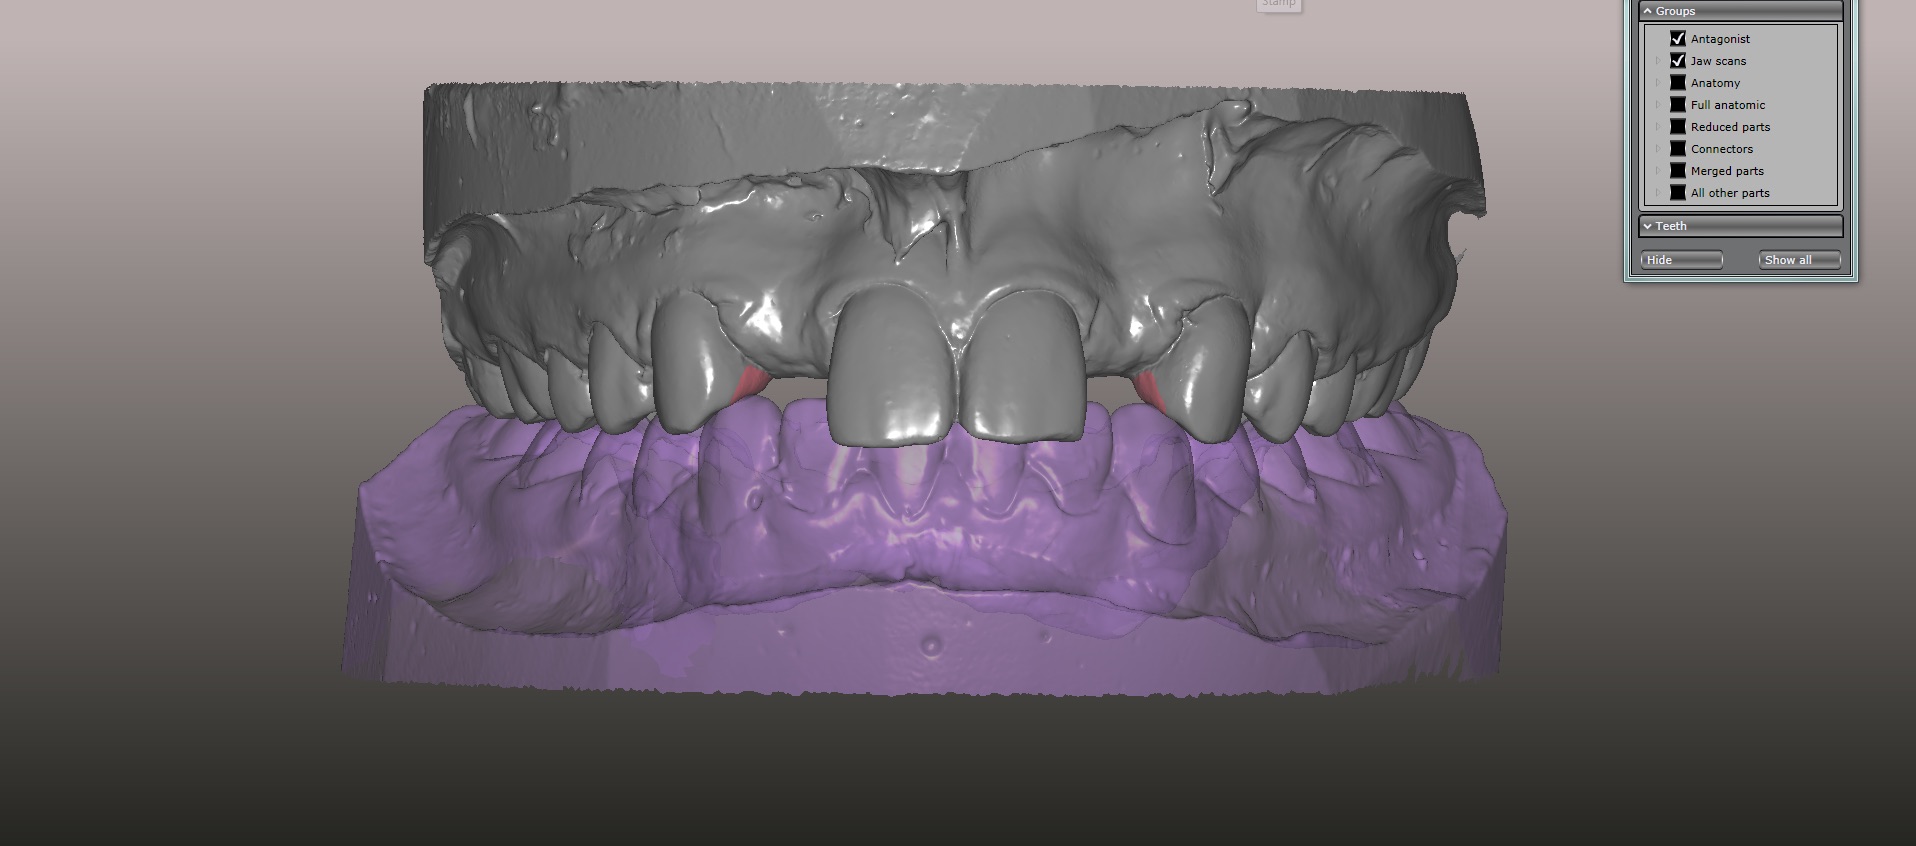

(15.) Models mounted in maximum intensity projection, allowing design of the retainer extensions on the lingual of the canines (in pink).

Figure 15